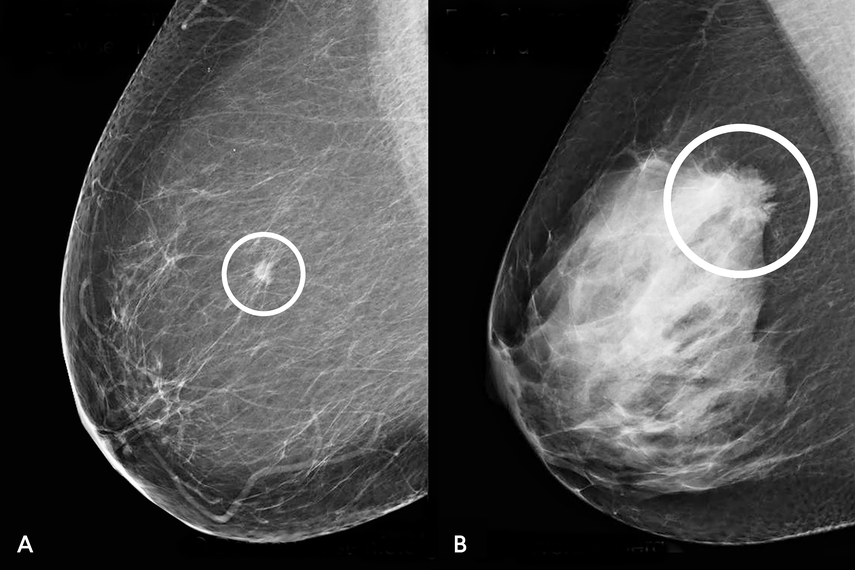

Todas ellas realizaron una mamografía, pero el primer grupo se cribó de forma convencional, es decir con la mirada de dos radiólogos independientes, mientras que los datos del segundo fueron examinados primero por una IA y luego por un solo radiólogo.

Los datos del estudio no arrojan luz sobre el riesgo de "sobrediagnóstico", es decir, la detección de lesiones que no se habrían convertido en cánceres peligrosos sin tratamiento.

Stephen Duffy, profesor de detección de cáncer en la universidad Queen Mary de Londres que no participó en el estudio, señala que la IA puede haber diagnosticado en exceso ciertas formas de cáncer de mama temprano, llamado carcinoma ductal in situ.